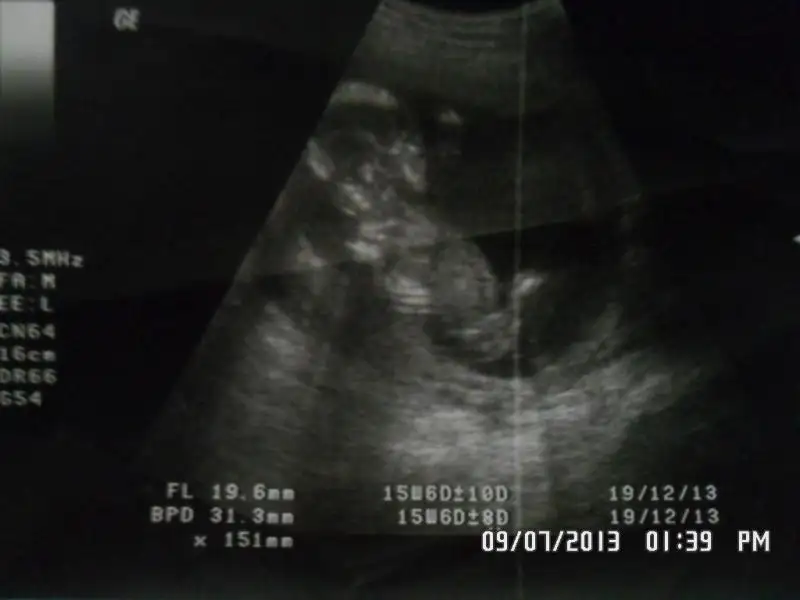

dr soylemeden siz gorun genital nub teorisi ( bebegin cinsiyeti)

kızlar benimkinede yorum yapın doktor erkeğe benziyor dedi.

Buda benim bebeğim 12+2 :emir_bebek::emir_bebek: